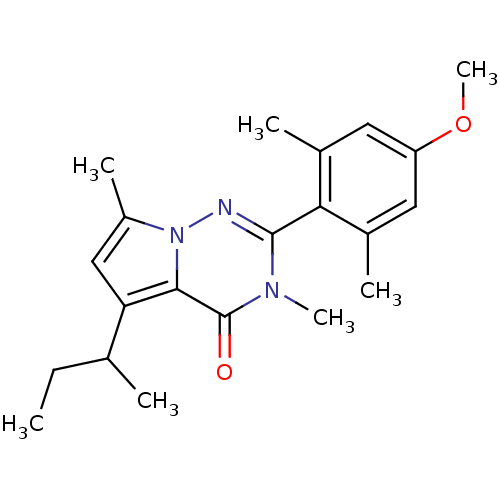

TargetCorticotropin-releasing factor receptor 1(Homo sapiens (Human))

Dupont Pharmaceuticals

Curated by ChEMBL

Dupont Pharmaceuticals

Curated by ChEMBL

Affinity DataEC50: 0.300nMAssay Description:Antagonist activity at human CRF1 receptor expressed in CHO-K1 cells assessed as CRF-stimulated cAMP accumulation by enzyme immunoassayMore data for this Ligand-Target Pair

Affinity DataEC50: 0.420nMAssay Description:Antagonist activity at CRF-R1 in mouse AtT-20 cells assessed as inhibition of human CRF induced cAMP accumulation after 30 mins by radioimmunoassayMore data for this Ligand-Target Pair

Affinity DataEC50: 0.440nMAssay Description:Antagonist activity at CRF-R1 in mouse AtT-20 cells assessed as inhibition of human CRF induced cAMP accumulation after 30 mins by radioimmunoassayMore data for this Ligand-Target Pair

Affinity DataEC50: 0.450nMAssay Description:Antagonist activity at CRF-R1 in mouse AtT-20 cells assessed as inhibition of human CRF induced cAMP accumulation after 30 mins by radioimmunoassayMore data for this Ligand-Target Pair